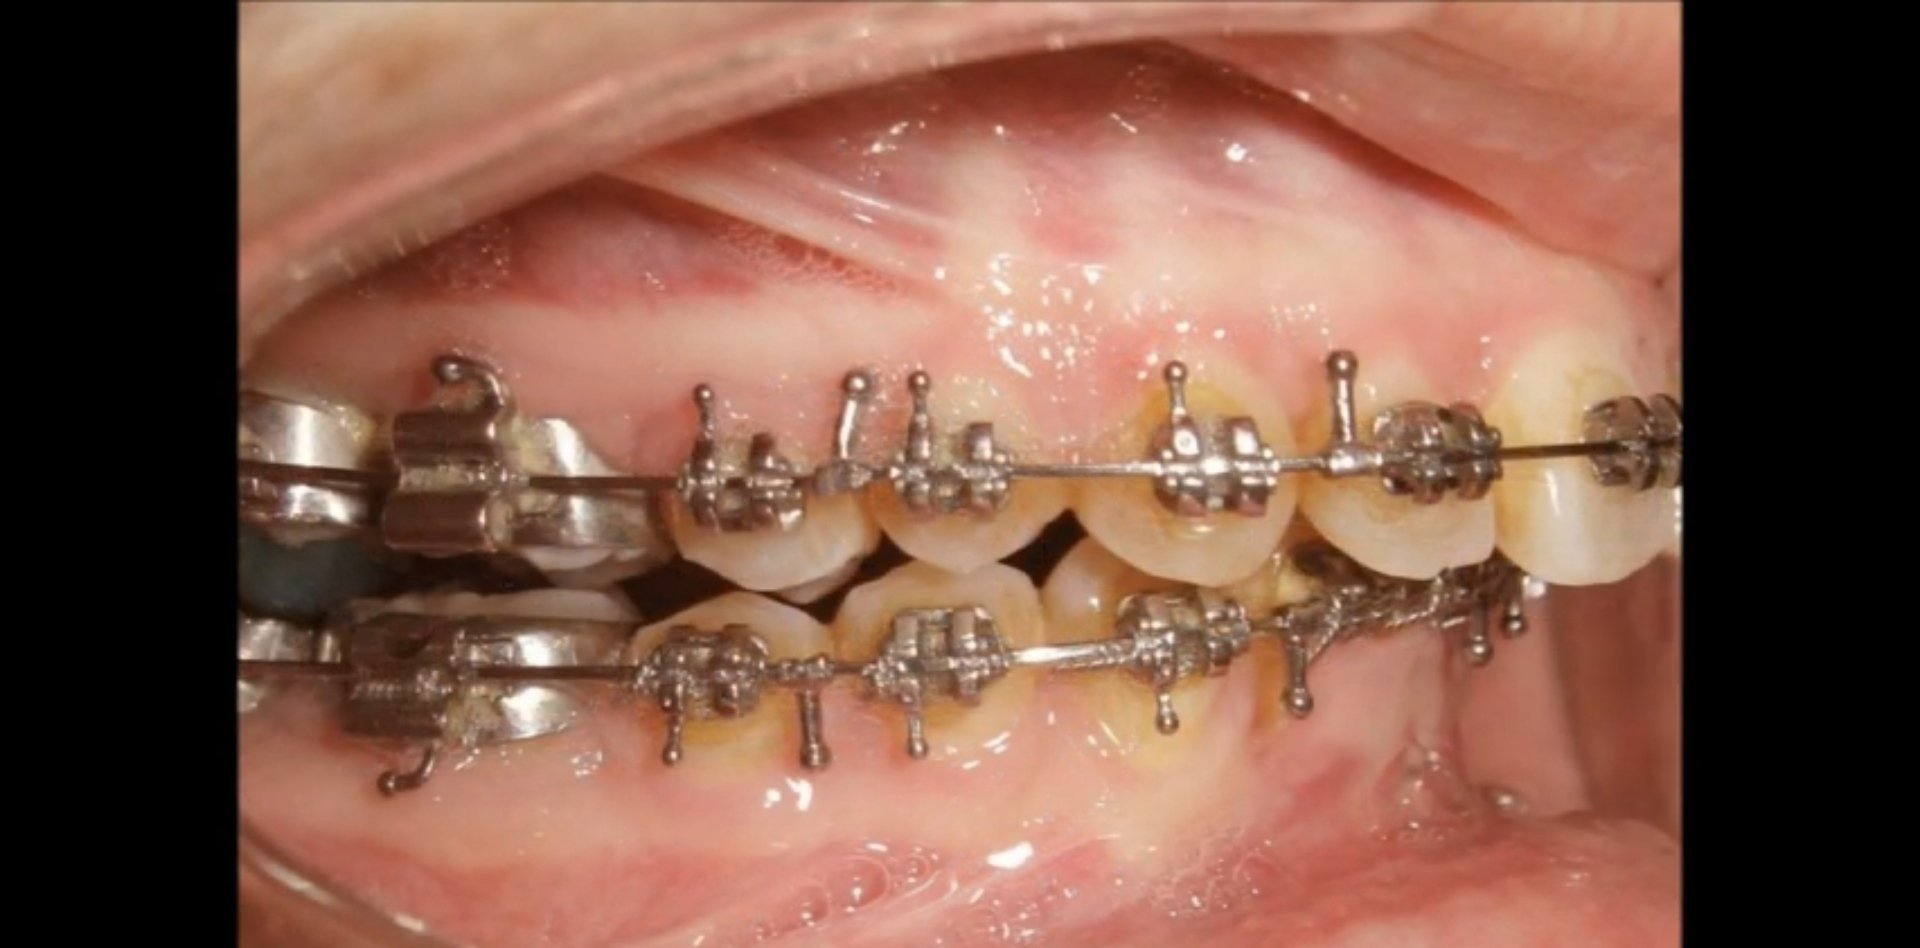

За почистване на зъбите с брекети се препоръчва използването на конци, четки и вода за уста. Конците се движат между дъгата и брекетите, а четките се използват с кръгови, вибриращи движения около венечната линия и върху брекетите. След отстраняване на брекетите се препоръчва използването на заменяеми ритейнъри и извършването на редовно почистване с конци, четки и вода за уста. В случай, че не сте доволни от резултата, потребителите споделят своя опит със смяна на ортодонт.